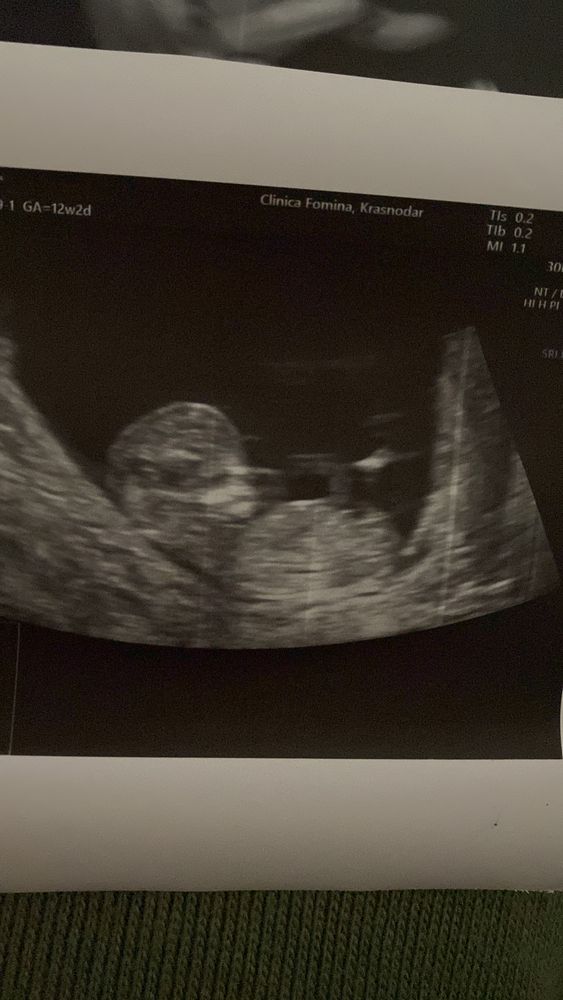

Анастасия, ну не знаю.. мне кажется, что это все же генетика, да и ракурс имеет значение) вот голова мальчика, например) совершенно не похоже на фотку выше Изображение

Faya, фото в 12 недель?)